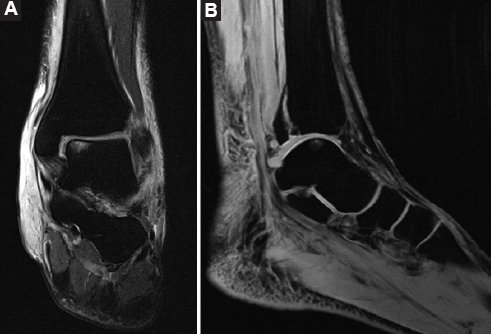

Varón de 49 años, sano, quien se ejercitaba regularmente con carreras y ciclismo seis veces por semana, y sin antecedentes de consumo de tabaco o alcohol, que acudió al servicio de urgencias después de sufrir una caída de bicicleta con traumatismo directo en su tobillo izquierdo. Experimentó un chasquido en el tobillo y no pudo identificar un mecanismo específico de lesión. Durante la evaluación inicial se constató incapacidad para la bipedestación, edema, limitación en los arcos de movimiento del tobillo y dolor a la palpación en el tercio medio de la diáfisis del peroné. Las radiografías mostraron una fractura espiroidea en el tercio medio de la diáfisis del peroné con desplazamiento posterior del tercer fragmento y una fractura de maléolo posteromedial desplazada (Fig. 1). Inicialmente se colocó una férula suropodálica posterior y se solicitó resonancia magnética de tobillo, en la cual se observaron fractura del maléolo posteromedial, ruptura del ligamento peroneoastragalino anterior, lesión condral en el margen medial del astrágalo con edema subcortical y ruptura de los fascículos profundos del complejo deltoideo (Fig. 2).

Figura 2. Resonancia magnética de tobillo izquierdo. A: corte coronal T2 que muestra lesión del deltoideo y zona de edema óseo en el astrágalo. B: corte sagital T2 que muestra fractura de maléolo posteromedial.